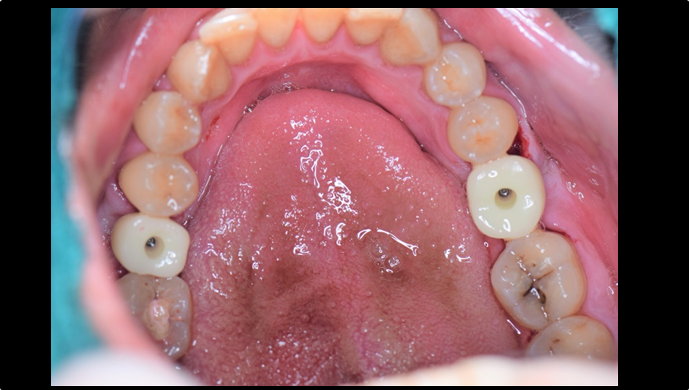

Clinical case: Extraction, immediate placement & loading using

R2GATE solution in aesthetic zone

- Courtesy of Dr. Jong-Cheol Kim, Korea-

Dr. Jong Cheol Kim, immediate loading, digital guided surgery, Digital ONE-DAY Implant, maxillary anterior, #21, guided surgery, immediate loading, AnyRidge, R2GATE, Mega ISQ, MEG Torq, R2GATE Full Surgical Kit

AnyRidge implant system, R2 Guide, R2GATE Full Surgical Kit, Mega ISQ